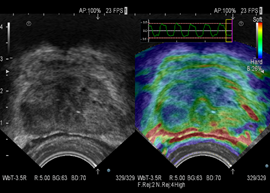

(Real-time Tissue Elastography?)

作为应用zei完善、覆盖zei全面的实时组织弹性成像技术,日立组织开展了国内zei早的弹性成像多中心研究项目,率先规范化、标准化。同时,日立弹性也在不断提升和优化,交响系列全新推出FLR、ASF等智能化测量技术,更精确高效的服务于临床诊断。